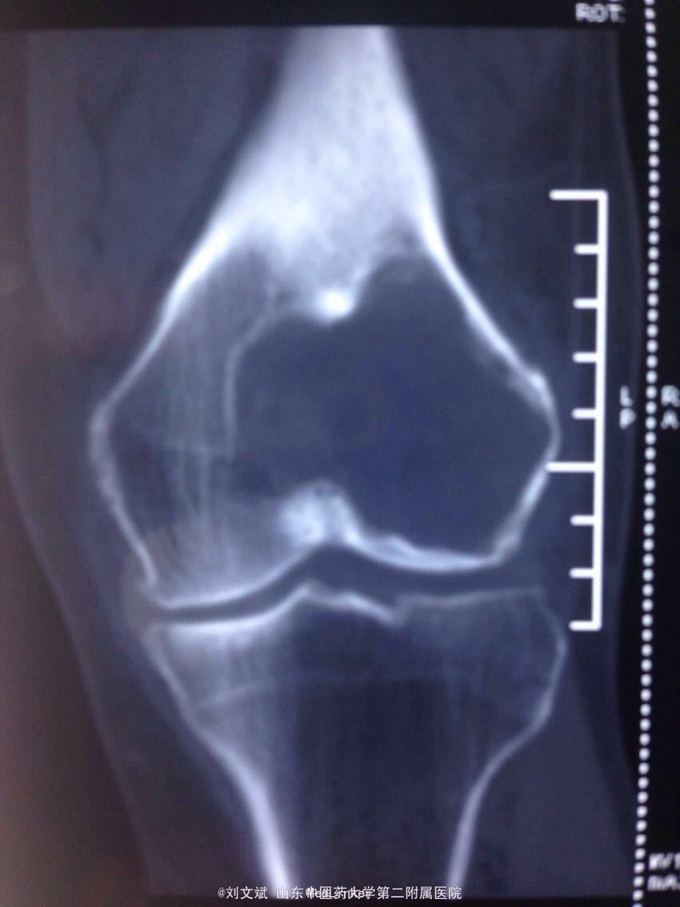

男性51岁,左膝关节疼痛不适10余年。因症状较轻,不影响活动,未曾系统诊治。一月前因扭伤致疼痛加重,拍片检查,见股骨远端骨质异常,进一步行CT示股骨髁占位病变,考虑骨囊肿。既往有高血压,糖尿病病史。近期无低热,体重下降。

诊断:左股骨远端占位 因皮质完整,行手术开窗刮除,自体髂骨及同种异体骨混合植骨填充治疗。切取组织送病理检查

刮除占位组织如图所示,送病理检查了,结果还没回来。 没有全身症状,像是原发灶,骨皮质完整,没有明显骨膜反应请专家们看看,什么可能性比较大? 补上病理结果和术后片子